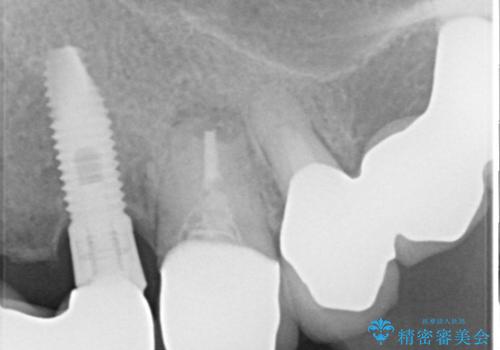

検査を行い、抜歯即時インプラント(1Dayインプラント)治療を行いました。

抜歯をしインプラント埋入と骨補填材を填入して仮歯までを1日で行う「抜歯即時埋入即時過重」の手術をし、3ヶ月後には、オールセラミックを被せて定期検診となりました。